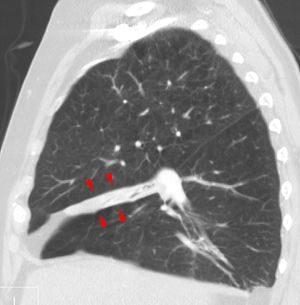

- التصوير المقطعي

في الانخماص المدوّر (متلازمة الرئة المطوية) ينهار الجزء الخارجي من الرئة ببطء نتيجة لتليّف وتقلّص طبقات الأغشية التي تغلف الرئة، وهذا ينتج مظهر مدوّر على الأشعة السينية قد يجعل الأطباء يخطئون ويعتقدون أنه ورم. الانخماص المدوّر عادة ما يكون من مضاعفات مرض يصيب الغشاء المغلف للرئة بسبب مادة الأسبستوس (الحرير الصخري)، و يمكن أن ينتج ايضاً من أنواع أخرى من التليف المزمن وتغلّظ أغشية الرئة.